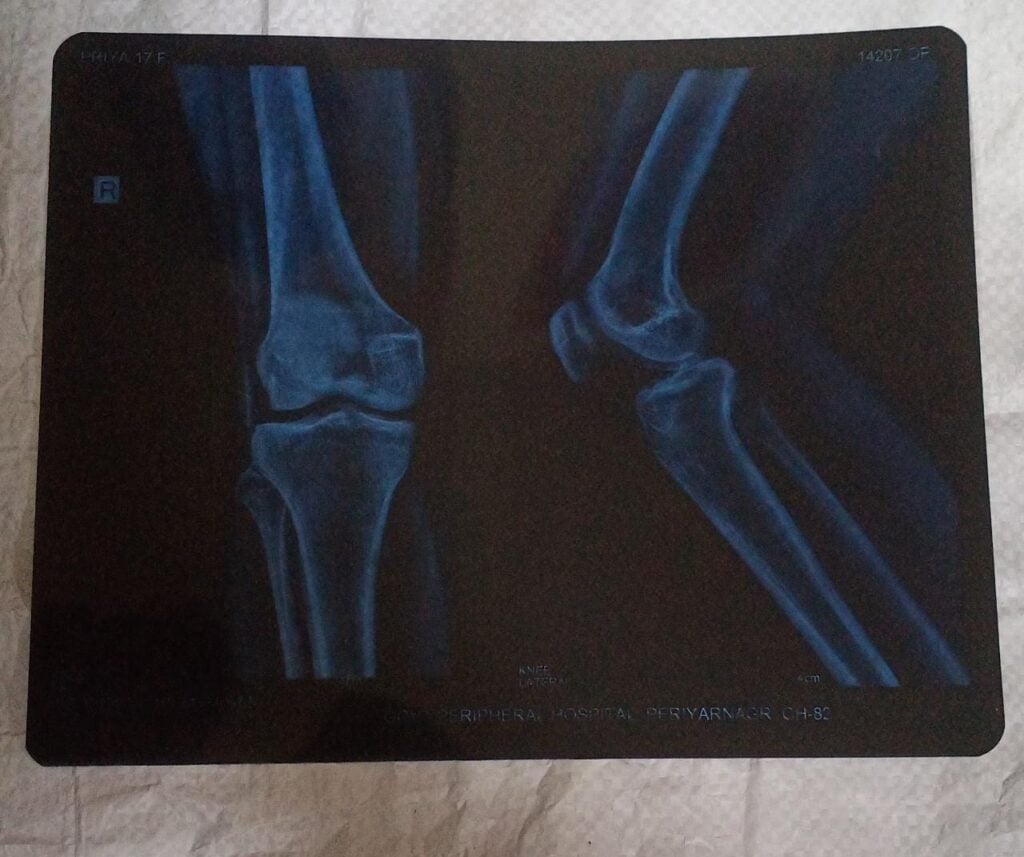

இதையடுத்து சென்னை ராஜீவ் காந்தி மருத்துவமனையில் பரிசோதனை செய்தபோது, காலில் சவ்வு விலகி இருப்பது தெரியவந்தது.

ராஜீவ் காந்தி மருத்துவமனையில் மாணவி பிரியாவிற்கு அறுவை சிகிச்சை செய்யப்பட்டதில் காயம் எவ்வாறு உள்ளது என்பதை பரிசோதனை செய்த பொழுது, காலில் தசைகள் அனைத்தும் அழுகக்கூடிய நிலையில் இருப்பது தெரியவந்துள்ளது.